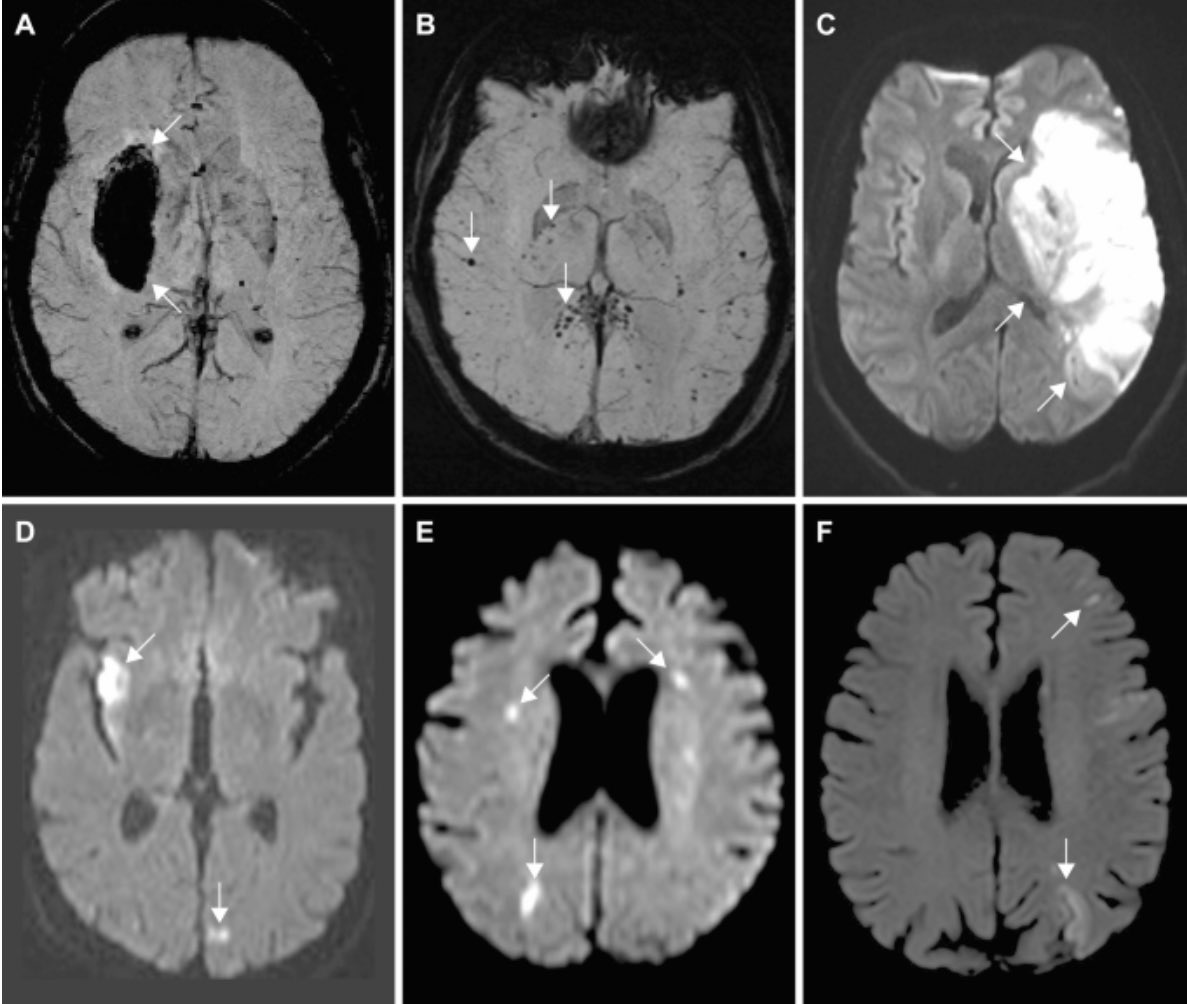

Recently published large study of brain MRI in acute #COVID shows vascular phenomena are common.

Here are some highlights….

bit.ly/4pX0Hu3Image 458 brains studied

First wave of pandemic (so not applicable to later/current variants)

Most common finding = ischaemic infarct (stroke)

See image B-F Image